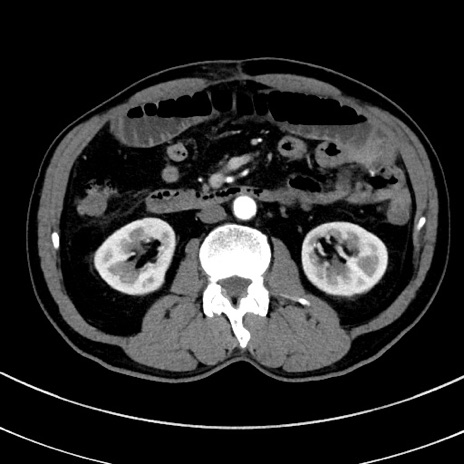

症例8(横断像)

【症例】 60歳代男性

【主訴】 黒色吐物

【現病歴】 4日前から嘔気自覚、2日前の朝食後にも嘔気あり、自分で手で嘔吐反射起こし嘔吐したところ血が混ざっていたため受診。

【既往歴】 5年前汎発性腹膜炎を伴う急性虫垂炎で手術、高血圧、前立腺肥大症、高脂血症

【身体所見】 腹部正中に手術癩痕あり 腹部平坦・軟圧痛なし膨満感あり

【データ】WBC 8400、CRP 4.54